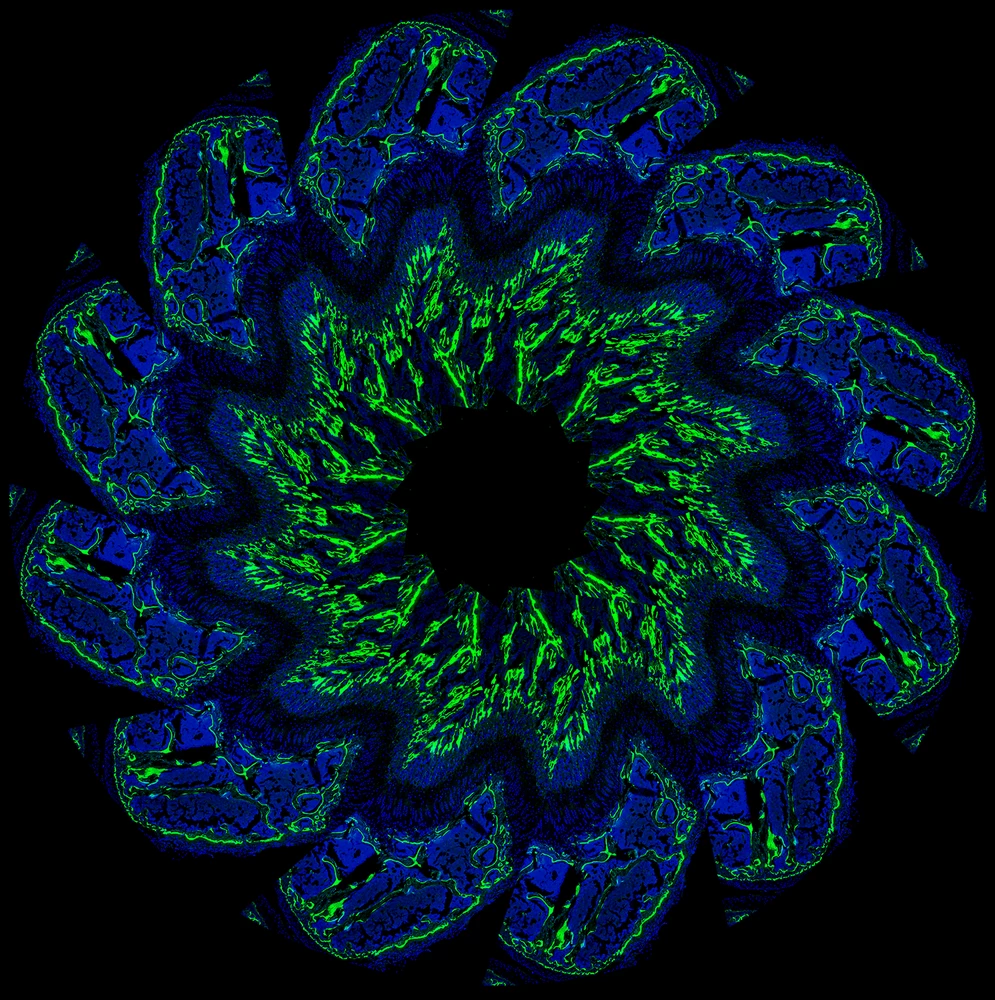

This “blossom” is made of overlapping images of a growth plate from the bone of a two-week-old mouse.

This is an arrangement of a growth plate from the femur of a two-week-old mouse. The image is repeated 12 times to create the blossom shape. New bone growth is stained green (1) and the nuclei of the surrounding cells are stained blue (2).

In juvenile vertebrates, the bones contain a thin layer of cartilage, which is called the growth plate. The growth plate is responsible for bone elongation. It accomplishes this goal by continually producing new cartilage, which then becomes remodeled into bone tissue. As the animal approaches its adult size, the growth plate function slows and eventually ceases.

In mice, a growth plate is about 75 micrometers thick, or roughly the same size as the width of a human hair.

This image was created using confocal microscopy.